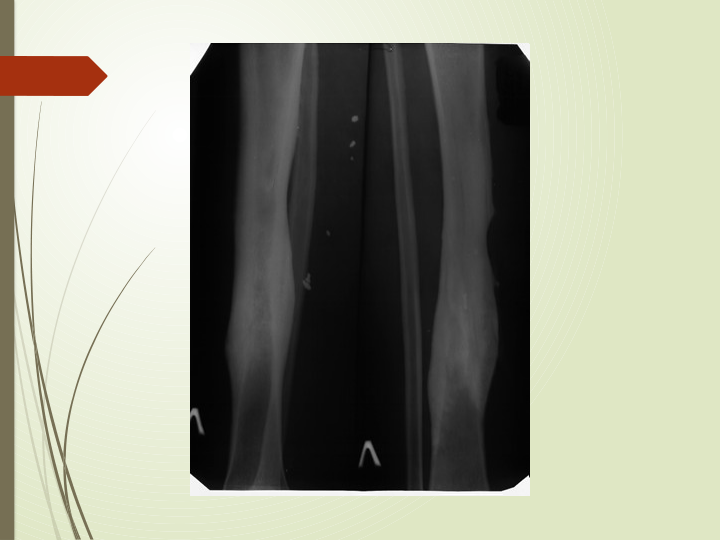

Polifokal (ikki darajali) sinish

 Bitta suyakda ikkita

singan bo'lsa, ular

polifokal yoki ikki

darajali yoriqlar

haqida gapirishadi.

Logotip